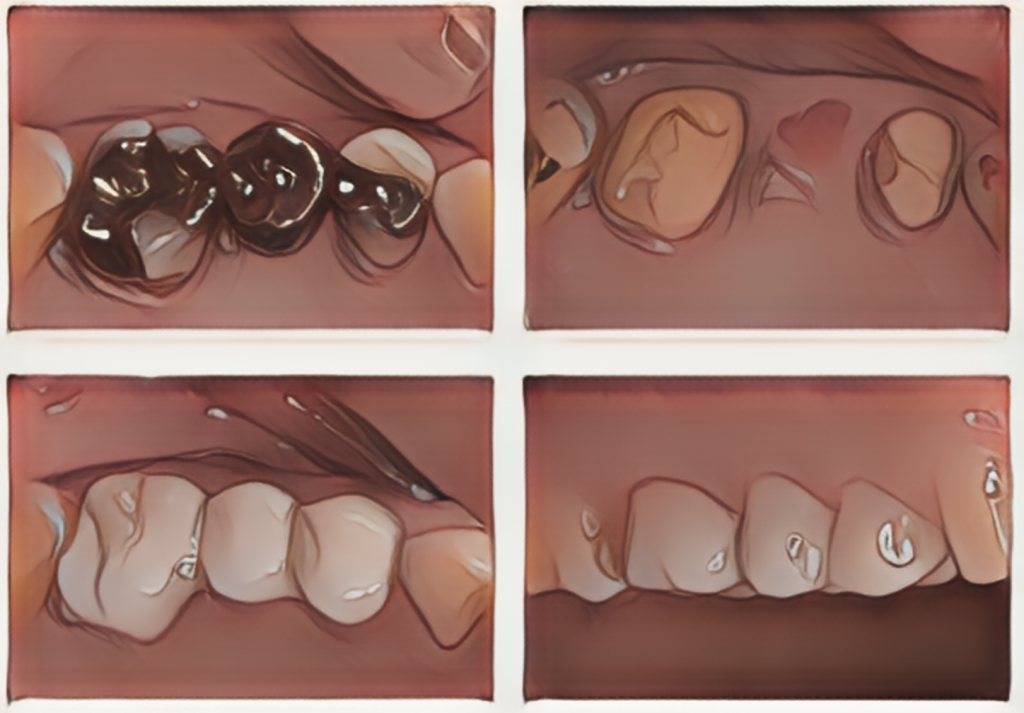

銀の詰め物を外したところ、広範囲の虫歯のため、かぶせ治療が必要な状況でした。

土台の歯の虫歯を除去したところ、神経を残した状態でブリッジ修復ができると判断できました。

ブリッジ修復が長期安定する条件としては、歯の神経を残せることや確実に清掃できる環境であることなどが挙げられます。また、ブリッジの土台にかかる力は本来の歯があった時よりも単純計算で1.5倍の力がかかるため、歯の支えがしっかりしていること(根の長さ、骨の支え)も有利な条件となります。

本症例は、これらすべての条件を満たしていたこと、そして周りの歯はすでに虫歯によって歯の構造を大きく失っていたこともあり追加で削る量も少なく、欠損部だけでなく奥歯全体の環境改善を図るためにブリッジ修復を選択しました。

治療終了時の状態です。材質はセラミックを用いないジルコニアという材料(フルジルコニアクラウン)を選択して、ブリッジ修復を行いました。強度があり軽く、ここ数年でそれなりの色調表現も可能になりました。セラミック修復に比べるとやや透明感は劣りますが、割れたり欠けたりする可能性が大きく軽減できることがメリットです。また、セラミック修復に比べると削る量も少なくなるため、土台の歯にも優しい方法になります。さらにツルツルに研磨して仕上げることで、かみ合わせの相手の歯を磨耗させるリスクが最も少ない方法でもあり、現在は奥歯のかぶせ治療の第一選択と考えております。